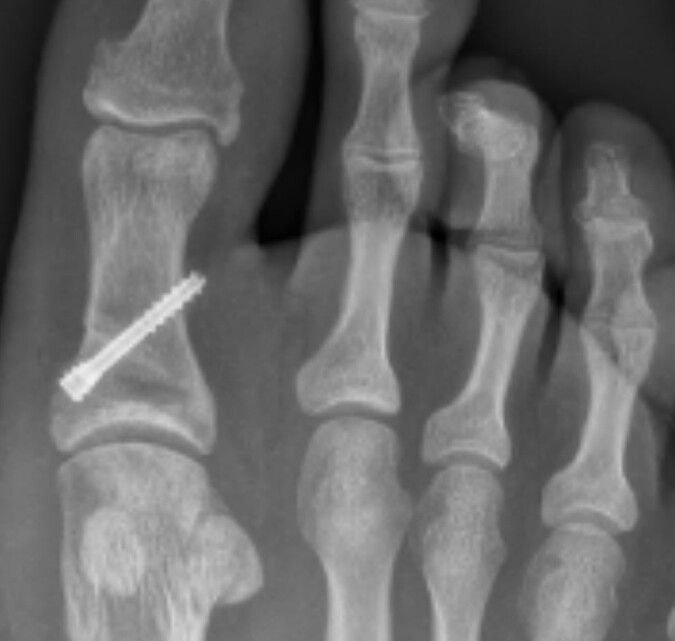

April 2024 I’d just come back from an amazing USA holiday and jumped back into a VFLW season. First game back hurt my big toe, don’t remember an action or a moment but this is where the pain started.

Fast forward to today, after 2 seasons of playing constantly in pain, rehab, countless exercises, taping, arts and crafts (IYKYK), cross training session, load management, MRI’s and X rays with no answer, training once a week just to get by, becoming besties with a moon boot, surgery in September and today 100 days since surgery a successful PAIN FREE return to run !! Yay

But its not just all of the physical pain and drain that goes with an injury, this injury had such a mental toll on me, more then I could ever had imagined. 2 years worth of uncertainty as to what the problem was and how we were going to fix it. Banter and running jokes about ‘Frogs dogs’ and ‘yeah I’m in a boot again’ ‘just wanted to get out of pre season’ are used to hide what was really being felt and bottled up inside. So many tears had at training, post games, in the car and in bed some visible to those around but most behind a closed door. I think it’s the uncertainty and constant worry that is definitely the worst feeling ever overtaking the physical pain.

I am fully aware it’s no ACL or career ending injury but I wanted to speak out to the other side of injuries that not everyone sees whether they are big or small. I am so thank full that I have the best circle of support people in friends, family, the EFC, sport psychs, physios and Doctors that have got me to this point today, a very happy girl who was once unsure if anything was going to fix her poor dog but today got through her first run pain free.